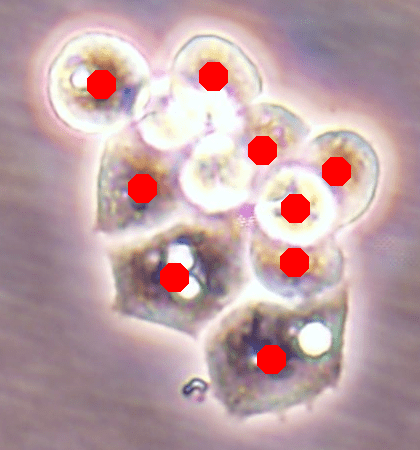

Since the main goal of this work is cell detection, our DeepDistance models define the estimation of an inner distance map as the main task and find regional maxima on this estimated map to detect cells. The motivation behind these choices is the fact that the inner distance definition gives sharp increases at cell centers and the locations with these sharp increases can be detected by finding regional maxima. Hence, to obtain accurate detections, one should estimate an inner distance map with distinct differences between the cell centers and their surrounding pixels such that these centers can be identified as regional maxima. That is, one should estimate a map consisting of sharp enough bright regions close to the cell centers. To improve the performance of the task of this inner distance estimation, our models take advantage of multi-task learning approach. This approach helps the models become more robust to avoid overfitting a task, compared to the approach of learning the same task alone with a single-task model (Caruana, 1997). To get more insight in this multi-task learning approach, this section visually analyzes the estimated maps of single-task and multi-task models.

![]() |

| (a) | (b) | (c) | (d) |

For the independent test samples given in Fig. 4, Fig. 6a shows the maps of the calculated inner distances when the ground truths are given. Figs. 6b, 6c, and 6d illustrate the inner distance maps estimated by the SingleInner method, the proposed DeepDistance model, and its extended version, respectively. SingleInner learns its map as a single-task whereas our models define auxiliary tasks and learn the inner distance map in parallel to these auxiliary tasks, forcing them to learn shared representations with a shared encoder path. The latter type of learning, which is an example of multi-task learning, is known to be effective for increasing the performance of individual tasks for many domains. We also observe this performance increase in the estimated maps given in Fig. 6. SingleInner cannot successfully detect the three cells shown inside red ellipses since it cannot produce sharp enough bright regions (with distinct enough estimated distances) for these cells. Although DeepDistance, which uses one auxiliary task, leads to brighter regions for these cells, they are still not sharp enough for two of them to be identified as regional maxima. The extended version of DeepDistance, which uses one more auxiliary task, does better job in inner distance estimations such that they have sharp enough bright regions for all of these three cells.

In this figure, it is worth to noting two points: First, all methods apply the h-maxima transform on their estimated maps beforehand to suppress noise, and hence, to prevent over-segmentations and false positives. If it was not applied, SingleInner might give regional maxima for some of the three cells even though the distances estimated for their centers were not that distinct (bright). However, that case would also give many over-segmented cells and false positives. Second, none of the methods identify the cell shown inside a blue ellipse although their estimated distances yield bright regions for this cell. It is due to the evaluation method, which matches an annotated marker and a detected cell based on the distance between them since a test set image does not have boundary annotations but just a dot on each cell. In our experiments, a distance threshold is set to 30, considering image resolutions and the average cell size. This threshold may give a few incorrect matchings especially for larger cells, (e.g., the cell shown inside the blue ellipse). Increasing this threshold solves the problem for this particular cell, but this time, it will result in many incorrect matchings of detected cells with distant markers (or vice versa).